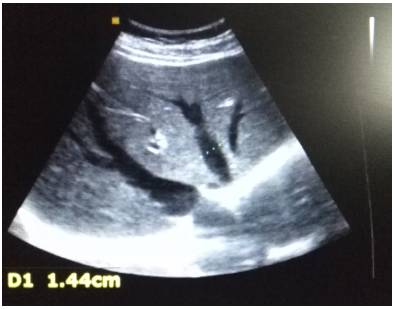

6、消化系统彩超

●左叶肝切面大小约71×65mm,右叶肝斜径:124mm。

●三支肝静脉增宽,肝左、中、右静脉内径分别约16mm、14mm、15mm。

●符合肝淤血声像图改变。

●胆囊多发结石。